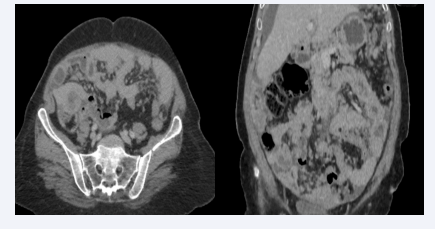

Multiple intraperitoneal tissue nodules above and below mesocoliaus associated with ascites of moderate abundance suggestive of  diffuse peritoneal carinosis in relation to ruptured appendicular mucocele

Figure 2: Multiple intraperitoneal tissue nodules above and below mesocoliaus associated with ascites of moderate abundance suggestive of diffuse peritoneal carinosis in relation to ruptured appendicular mucocele